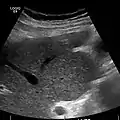

تستخدم أشعة الموجات فوق الصوتية بشكل روتيني في تقييم مدى تشمع الكبد، حيث إنها قد تظهر الكبد المتشمع في مراحله المتقدمة في شكل كبد صغير وعقيدي الشكل، بالإضافة إلى زيادة ارتجاع الصدى في الأشعة وظهور أجزاء غير منتظمة الشكل. كذلك من الممكن أن تُظهر أشعة الموجات فوق الصوتية وجود سرطان بخلايا الكبد وارتفاع ضغط الدم في الوريد البابي ومتلازمة بود-كياري (من خلال تقييم معدل تدفق الدم في الوريد الكبدي).

والجدير بالذكر أنه ظهر نوع جديد من الأجهزة، جهاز فايبروسكان (الإيلاستويد العابر)، يستخدم الموجات المرنة لتحديد مدى تيبس الكبد والذي يمكن تحويله نظريًا إلى درجة توضح مدى تشمع الكبد على أساس مقياس ميتافير METAVIR. ويعطي جهاز فايبروسكان صورة بالموجات فوق الصوتية للكبد (من 20-80 ملليمتر) إلى جانب قراءة الضغط (بالكيلو باسكال). ويمكن إجراء هذا الاختبار أسرع من أخذ العينة (عادةً ما يستغرق 2.5-5 دقائق) وهو غير مؤلم بالمرة. هذا بالإضافة إلى أن هذه الطريقة في التشخيص تعطي نتيجة منطقية لها علاقة بدرجة تشمع الكبد.[18]